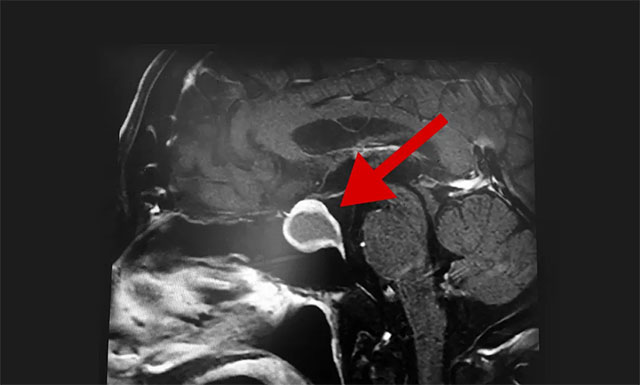

隨后,患者進(jìn)行了頭部鞍區(qū)MRI平掃+增強(qiáng),結(jié)果顯示:蝶鞍部顯著擴(kuò)大,鞍區(qū)見(jiàn)一不規(guī)則腫塊,大小約為2厘米X2.7厘米X1.9厘米,病變向鞍上生長(zhǎng),突入鞍上池,推移視交叉,向下生長(zhǎng),鞍底受壓變薄,與右側(cè)海綿竇部分解剖結(jié)果分界不清。

▲ 影像顯示,腫瘤已嚴(yán)重壓迫患者視神經(jīng)

根據(jù)患者檢查結(jié)果,潘仁龍主任介紹,患者之所以視物模糊就是因?yàn)榇贵w腫瘤向鞍上生長(zhǎng),突入鞍上池,壓迫到視神經(jīng)傳導(dǎo)物,而使得患者視物范圍變小,顳側(cè)、鼻側(cè)視野缺損,表現(xiàn)為進(jìn)行性視力下降、突然頭痛并視力下降。一般1-3cm的大腺瘤或大于3cm的巨大腺瘤,都會(huì)引起不同程度的視力問(wèn)題。